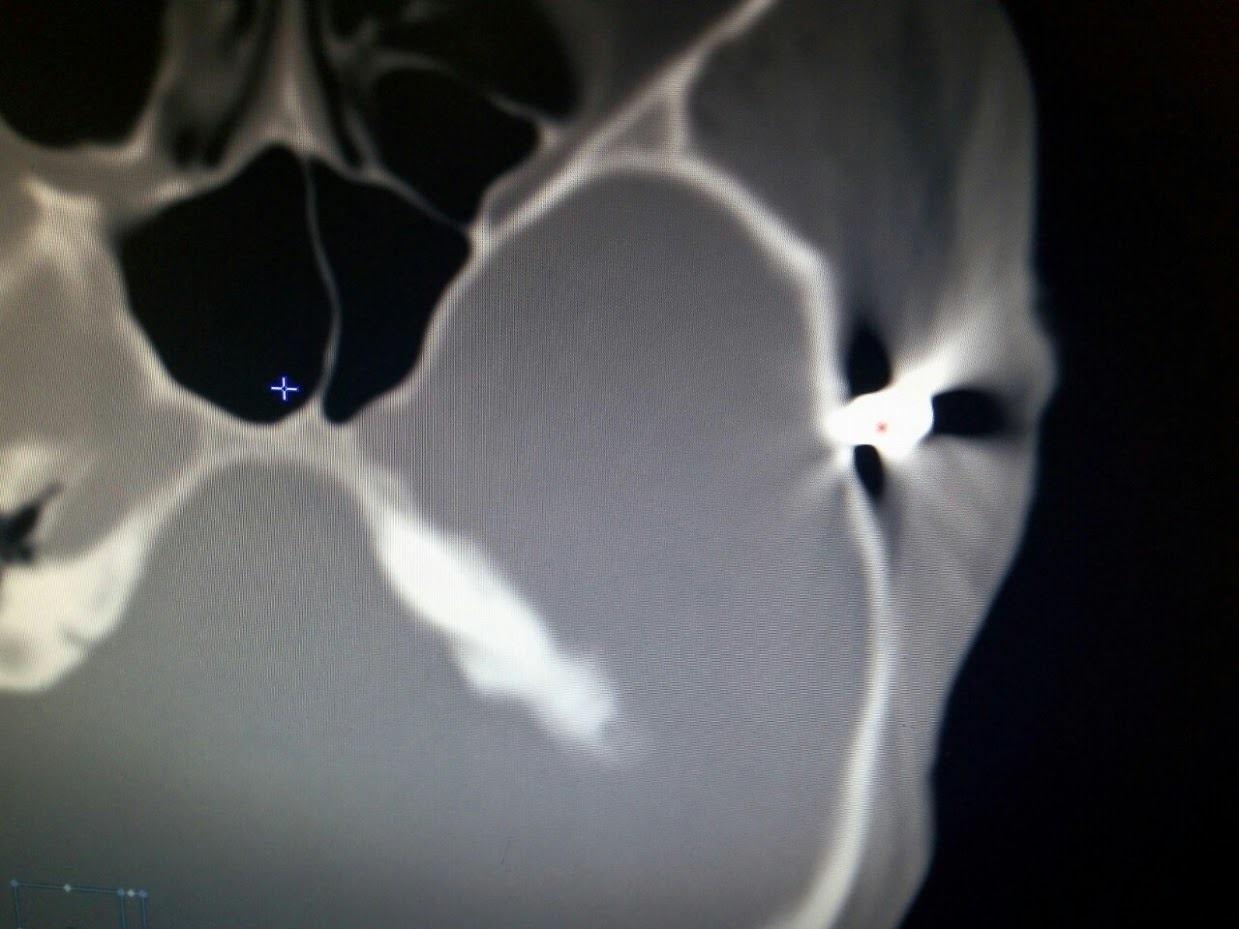

“Осколок в скроню. Руслан 35 років. Доставлений бортом з Авдіївки в лікарню Мечникова. Нейрохірургічна операція — прихід до тями. Спілкується з рідними”, — зазначає лікар.

К смерти не все готовоОсколок в висок.Руслан 35 лет. Доставлен бортом из Авдеевки в больницу Мечникова.Нейрохирургич…